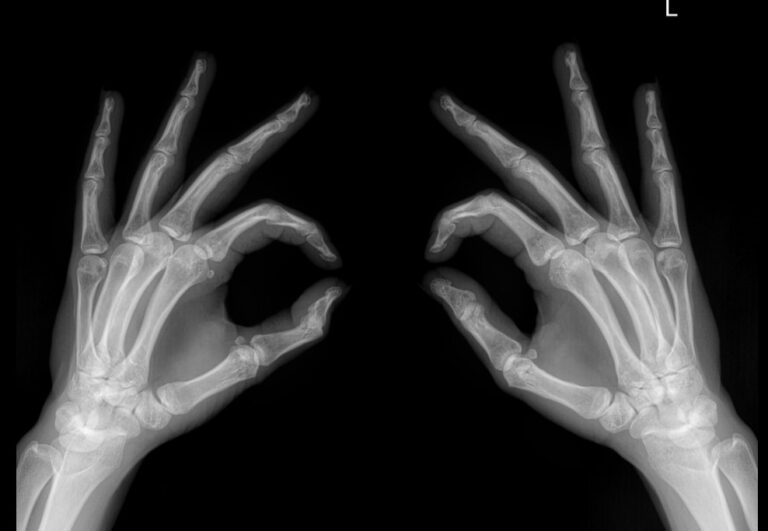

Рентген костей и суставов ― стандартная диагностическая процедура. Она основана на проникающей способности рентгеновского излучения, которое по разному задерживается в тканях разной плотности. Соответственно, изображение тканей на снимке будет в виде пятен также разных оттенков серого, от белого до практически черного. Как наиболее плотные, кости визуализируются как самые яркие. Современная аппаратура испускает минимальное излучение, составляющее минимальную часть от предельно допустимой годовой дозы.

Хронические системные патологии обычно поражают дистальные отделы верхних конечностей одновременно. Именно для этого и требуется снимок обеих кистей. В случае травмы или выявления врожденной аномалии рентгенограмма двух рук необходима для сравнения анатомических особенностей.

Диагностику выполняют без подготовки. Пациент закатывает рукава, снимает с рук все украшения, надевает защитный фартук и садится к снимочному столу. Руки на пластину детектора обычно кладут ладонями вниз и разводят пальцы, локти тоже лежат на столе. Существует и косая укладка, когда кисти кладут боком, но указания для этого должны быть в направлении.